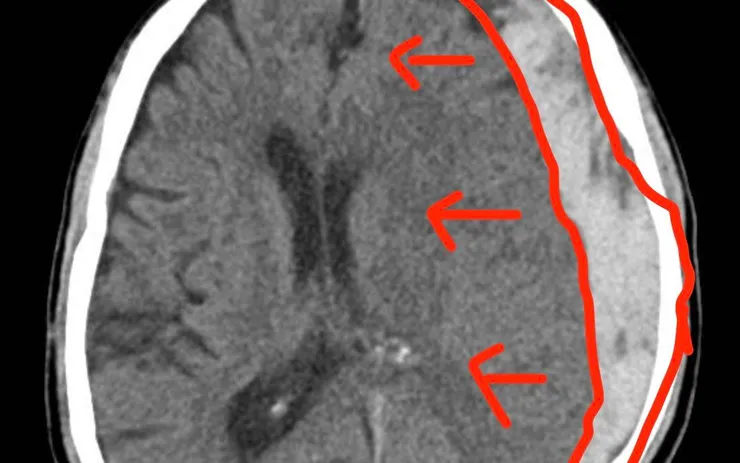

Kết quả chẩn đoán hình ảnh cho thấy bệnh nhân bị tụ máu dưới màng cứng cấp tính gây chèn ép não nặng. Đây là tình trạng cấp cứu ngoại khoa, có nguy cơ tử vong cao nếu không được can thiệp kịp thời.